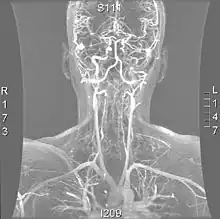

A reconstruction of the vertebral arteries from a CT scan, seen from the front. From the bottom, V1 is from the subclavian artery to the foramina, V2 is from the foramina to the second vertebra, V3 is between the foramina until entry into the skull, and V4 is inside the skull embedded in the dura mater. They merge into the basilar artery, which then divides into the posterior cerebral artery.

The vertebral arteries arise from the subclavian artery, and run through the transverse foramen of the upper six vertebrae of the neck. After exiting at the level of the first cervical vertebra, its course changes from vertical to horizontal, and then enters the skull through the foramen magnum. Inside the skull, the arteries merge to form the basilar artery, which joins the circle of Willis. In total, three quarters of the artery are outside the skull; it has a high mobility in this area due to rotational movement in the neck and is therefore vulnerable to trauma. Most dissections happen at the level of the first and second vertebrae. The vertebral artery supplies a number of vital structures in the posterior cranial fossa, such as the brainstem, the cerebellum and the occipital lobes. The brainstem harbors a number of vital functions (such as respiration) and controls the nerves of the face and neck. The cerebellum is part of the diffuse system that coordinates movement. Finally, the occipital lobes participate in the sense of vision.[1]

Magnetic resonance angiogram of the neck vessels in a person with Ehlers-Danlos syndrome type IV; it shows a dissection of the left internal carotid artery, dissection of both vertebral arteries in their V1 and V2 segments and a dissection of the middle and distal third of the right subclavian artery. Such striking episodes of dissection are typical for this "vascular" subtype of Ehlers-Danlos syndrome.

Various diagnostic modalities exist to demonstrate blood flow or absence thereof in the vertebral arteries. The gold standard is cerebral angiography (with or without digital subtraction angiography).[3][18][19] This involves puncture of a large artery (usually the femoral artery) and advancing an intravascular catheter through the aorta towards the vertebral arteries. At that point, radiocontrast is injected and its downstream flow captured on fluoroscopy (continuous X-ray imaging).[20] The vessel may appear stenotic (narrowed, 41–75%), occluded (blocked, 18–49%), or as an aneurysm (area of dilation, 5–13%). The narrowing may be described as "rat's tail" or "string sign".[1] Cerebral angiography is an invasive procedure, and it requires large volumes of radiocontrast that can cause complications such as kidney damage.[20] Angiography also does not directly demonstrate the blood in the vessel wall, as opposed to more modern modalities.[1][2] The only remaining use of angiography is when endovascular treatment is contemplated (see below).[1]

More modern methods involve computed tomography (CT angiography) and magnetic resonance imaging (MR angiography). They use smaller amounts of contrast and are not invasive. CT angiography and MR angiography are more or less equivalent when used to diagnose or exclude vertebral artery dissection.[18] CTA has the advantage of showing certain abnormalities earlier, tends to be available outside office hours, and can be performed rapidly.[1] When MR angiography is used, the best results are achieved in the T1 setting[2] using a protocol known as "fat suppression".[1][2][3] Doppler ultrasound is less useful as it provides little information about the part of the artery close to the skull base and in the vertebral foramina, and any abnormality detected on ultrasound would still require confirmation with CT or MRI.[1][2][3]